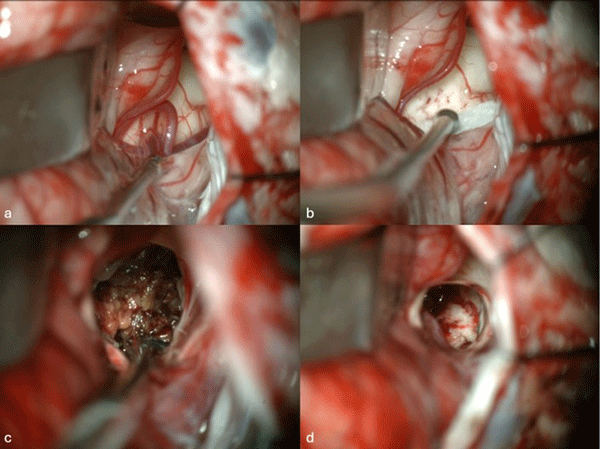

Figura 1. Imágenes intraoperatorias bajo microscopía. Craneotomía suboccipital lateral. Se ingresa al mesencéfalo desde posterior por una ruta supracerebelosa infratentorial lateral. A y B) Corticotomía en surco mesencéfalo lateral. C) Identificación y resección en bloque de la malformación cavernomatosa. D) Revisión del lecho, sin remanente.